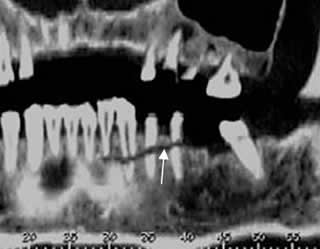

Fig 75. Trauma.

A: TAC axial, B: TAC reconstrucción coronal y C: TAC reconstrucción 3 D. Fractura conminuta, que afecta el borde inferior de la sínfisis mandibular. Por su localización, debe sospecharse lesión del canal dentario.